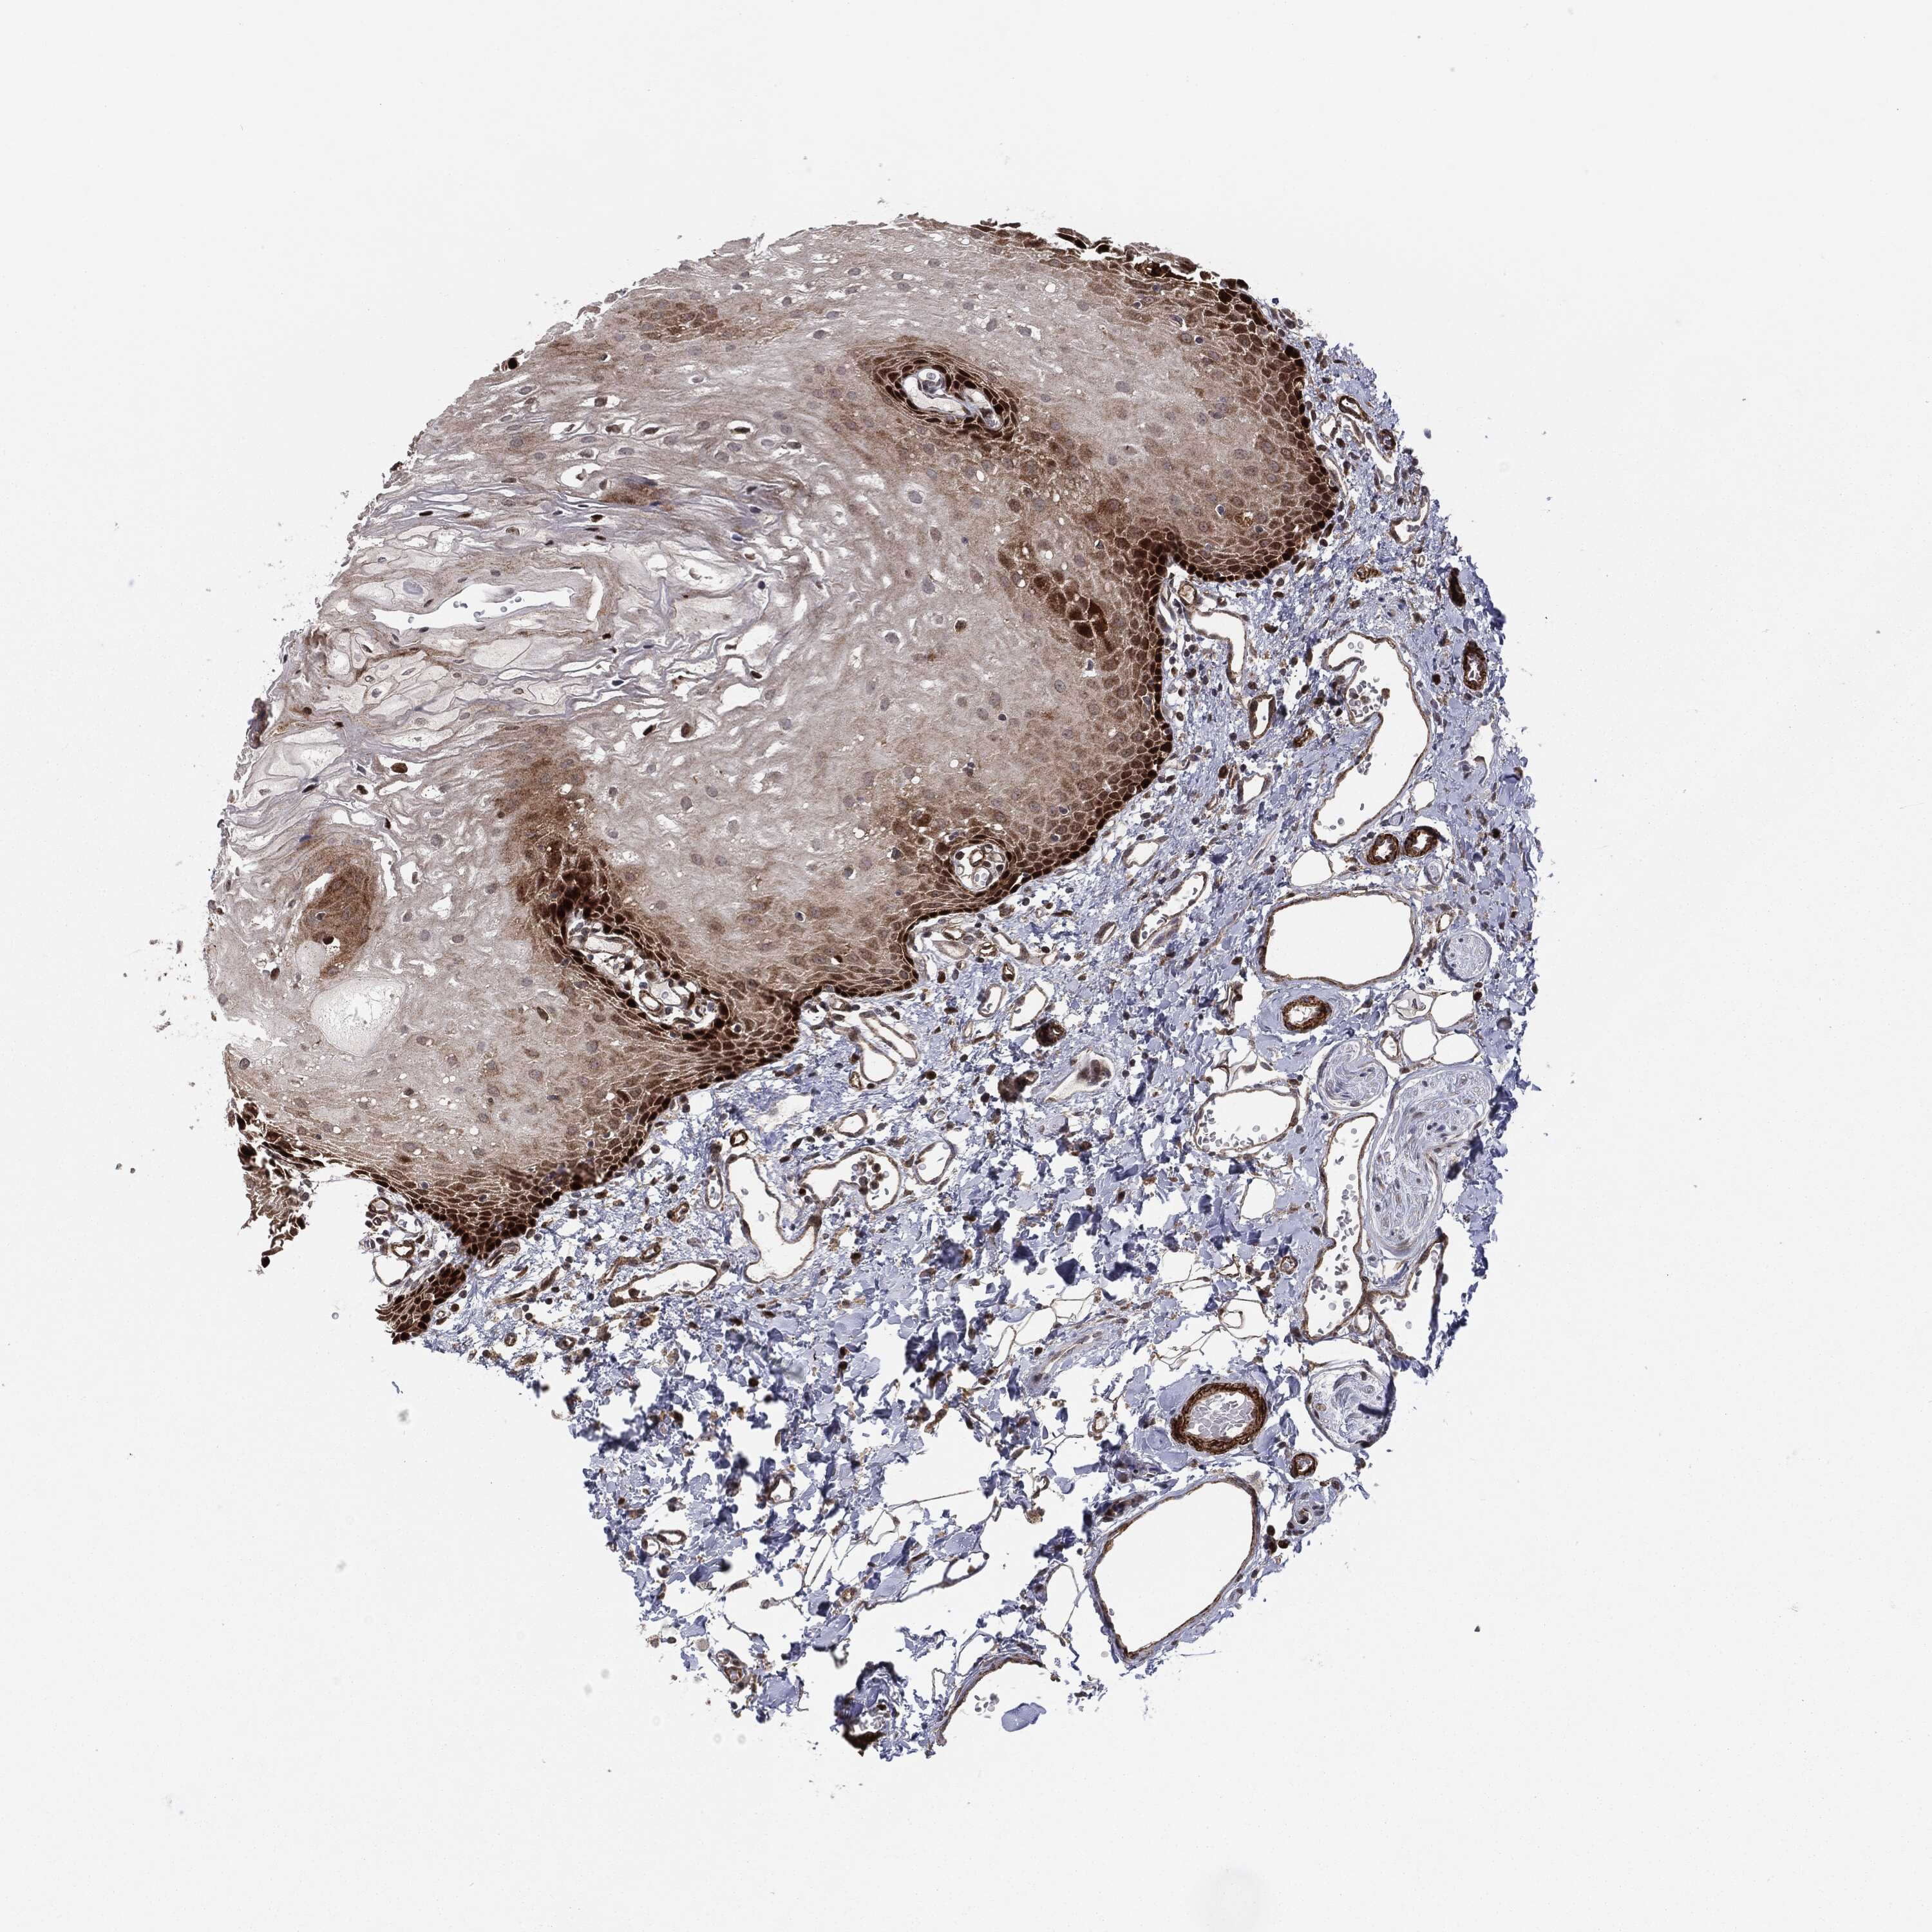

ORAL MUCOSA - Antibody stainingi

Antibody staining in the annotated cell types in the current human tissue is reported as not detected, low, medium, or high, based on conventional immunohistochemistry profiling in selected tissues. This score is based on the combination of the staining intensity and fraction of stained cells.

Each image is clickable and will lead to virtual microscopy that enables deeper exploration of all samples and also displays staining intensity scores, fraction scores and subcellular localization as well as patient and tissue information for each sample.

Antibody HPA031335Antibody CAB004076Antibody CAB080153Antibody CAB080157

Squamous epithelial cells MediumNot detectedNot detectedMedium